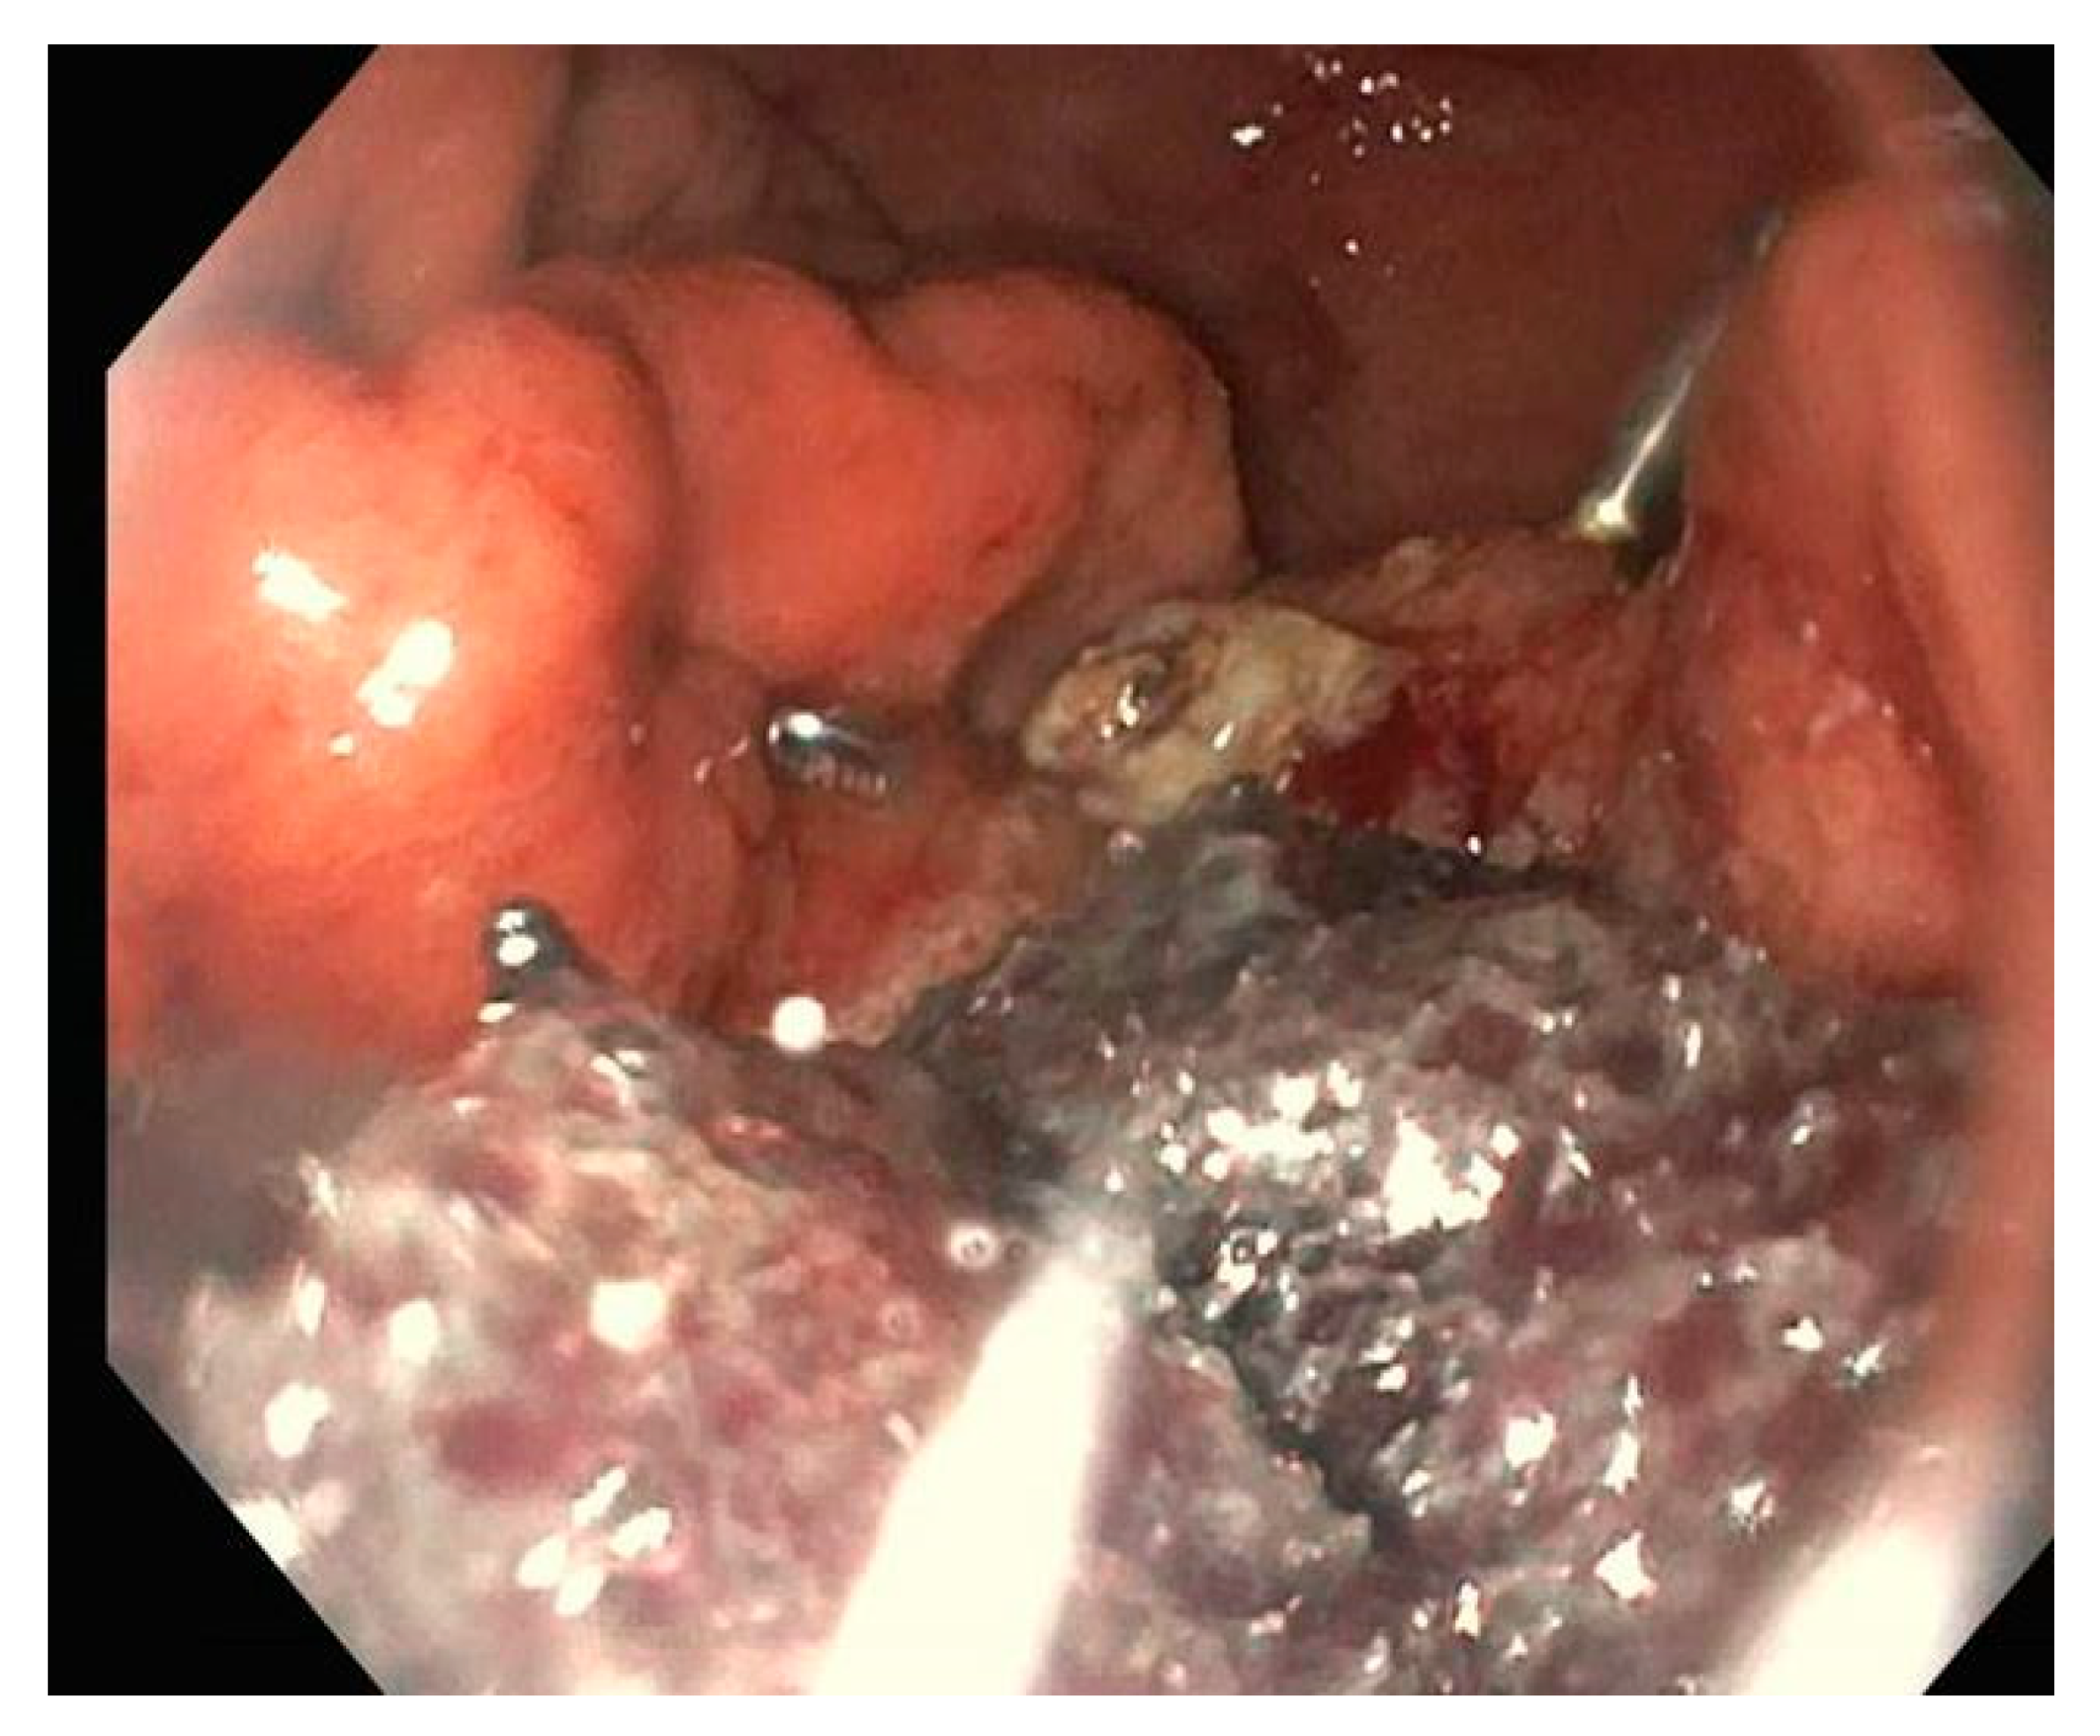

2. Endoclips